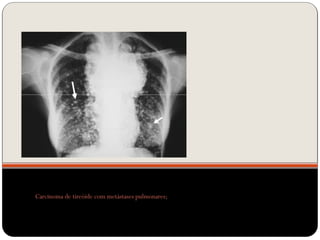

Nódulos pulmonares múltiplos

 Causas mais comum em adultos:

neoplasia metastática (diversos diâmetros,

densidade de tecido mole, raramente calcificada, exceto

osteossarcoma)

doença infecciosa (fúngicas e micobacterianas);

Carcinoma de tireóide com metástases pulmonares;